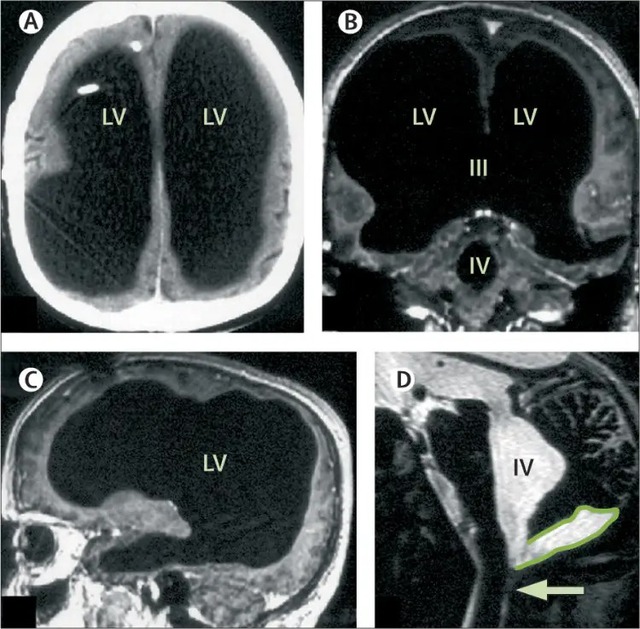

Những tưởng bệnh đã được khắc phục, nhưng 30 năm sau, khi ông bước sang tuổi 44, tình trạng yếu chân trái tái phát. Các bác sĩ tại Bệnh viện Marseille (Pháp) chỉ định chụp CT và MRI, và kết quả đã khiến toàn bộ ekip y khoa sửng sốt: não của ông gần như biến mất. Khoảng 75% đến 90% mô não bị tiêu hủy, thay vào đó là các khoang rỗng chứa đầy dịch não tủy.

Những hình ảnh chụp cộng hưởng từ cho thấy các thùy trán, thùy đỉnh, thùy thái dương và thùy chẩm - những khu vực đảm nhiệm tư duy, ngôn ngữ, cảm xúc và thị giác đều teo lại thành một lớp mỏng bao quanh hộp sọ. Trong điều kiện bình thường, tổn thương ở những vùng này sẽ dẫn đến suy giảm nghiêm trọng nhận thức, trí nhớ hoặc thậm chí rơi vào trạng thái sống thực vật.

Được mô tả lần đầu tiên trên tạp chí The Lancet vào năm 2007, trường hợp của người đàn ông dường như bị mất hầu hết não đã khiến các nhà khoa học bối rối.